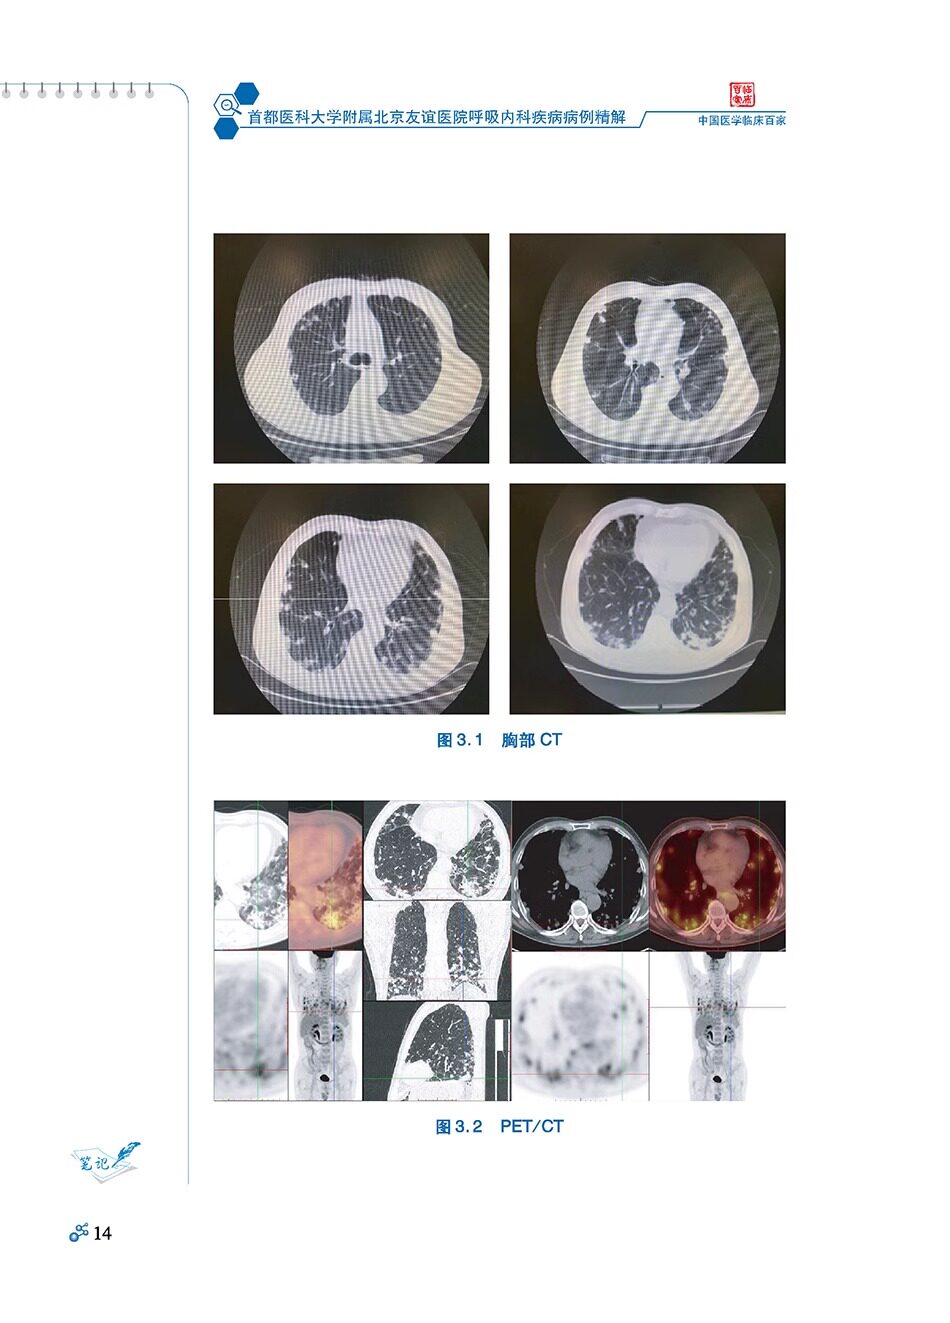

《首都医科大学附属北京友谊医院呼吸内科疾病病例精解》临床工作中只有不断对诊治过的病例进行分析、归纳和追踪,总结经验教训,复习相关文献,才能不断提高临床医生的诊疗水平。正确的诊断来源于详细地询问病史、细致地体格检查、合理必要的检验。在呼吸系统疾病的诊断中,离不开胸部CT检查、支气管镜检查,同时细胞及组织的病理诊断对呼吸科许多疾病有诊断价值。

本书选取了30个临床实例,多数病例是经过临床反复讨论会诊和追踪复查才明确诊断的,内容涉及肿瘤、炎症性疾病、结核病、胸膜疾病、肉芽肿疾病、肺血管及大气道疾病等呼吸系统病种。本书把影像学、气管镜下所见和病理学检查结果,一起呈现给大家,并对相关疾病进行了复习,希望能对呼吸内科专业的研究生和呼吸内科同仁有一些帮助。